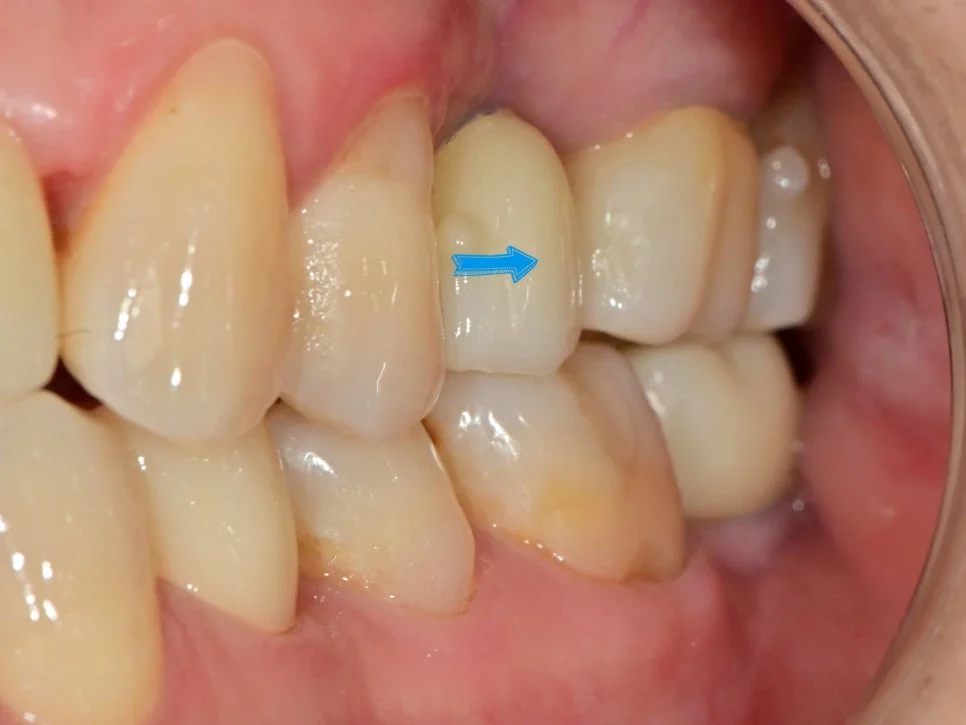

사례 1: 임플란트 보철 재제작으로 음식물 끼임 해결

왼쪽 아래 잇몸의 통증을 호소하신 환자분입니다.

임플란트 음식물 끼임 잇몸 부음 사진

음식물이 고여 있고 주변 잇몸이 부어있는 상태

임플란트와 인접 치아 사이 틈새

임플란트와 바로 앞 치아 사이가 문제

사진을 보면 음식물이 고여 있고 주변 잇몸은 많이 부어있는 양상인데요. 임플란트와 그 바로 앞 치아 사이가 문제입니다.